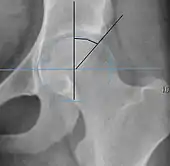

| Center-edge angle of Wiberg | ![]() |

The superior-lateral coverage of the femoral head. | |